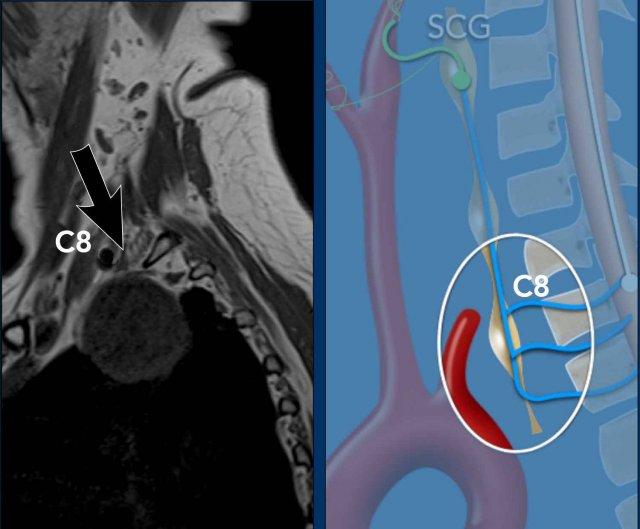

Preganglionic- 2nd order neuron

Tế bào thần kinh hạch trước hay tế bào thần kinh bậc hai nằm ở chất xám trung gian bên của tủy sống (trung tâm thể mi tủy sống của Budge-Waller) giữa C8 và T2.

Các sợi hậu hạch thoát ra ở rễ tủy sống bụng C8, T1 và T2, đi qua hạch cổ dưới (hay hạch sao, do hợp nhất với hạch ngực thứ nhất tạo thành hạch cổ-ngực), hạch cổ giữa, sau đó tạo synapse tại hạch cổ trên.

Hạch cổ dưới (ICG) nằm ở phía sau động mạch đốt sống, giữa mỏm ngang của đốt sống C7 và xương sườn thứ nhất.

Hạch cổ giữa (MCG) nằm ở mức sụn nhẫn C6, phía trong của củ cảnh và phía trước – trên của động mạch giáp dưới.

Hạch cổ trên (SCG) nằm ở mức C2-C3, phía sau bao cảnh và phía trước cơ đầu dài.

Bệnh nhân nam trẻ tuổi bị tai nạn khi tham gia đua xe mô tô địa hình.

Bệnh nhân được nhập vào khoa ICU với nhiều chấn thương.

Sau ba ngày, bệnh nhân hồi phục ý thức và được ghi nhận có liệt nửa người bên phải, không thể giải thích bằng bất kỳ tổn thương não nào.

Bệnh nhân cũng có hội chứng Horner bên phải.

Hình ảnh

CT lúc nhập viện cho thấy gãy mỏm ngang C7 và gãy xương sườn thứ nhất (đầu mũi tên).

Trên CECT có hiện tượng thoát thuốc cản quang cho thấy đang chảy máu tích cực (vòng tròn).

Continue with the MRI…

Đầu tiên, siêu âm vùng cổ được thực hiện để tìm kiếm tổn thương đứt rễ thần kinh, tuy nhiên việc khảo sát này bị hạn chế do các thay đổi chấn thương ở vùng này.

Sau đó, chụp MRI được thực hiện.

Hình ảnh cắt ngang cho thấy sự tăng cường tín hiệu của các rễ thần kinh, gợi ý tổn thương đám rối thần kinh cánh tay.

Cũng lưu ý tổn thương phần mềm cạnh cột sống bên phải.

Continue….

Ngoài ra, hình ảnh T2W cho thấy một số tín hiệu cao nhẹ trong tủy sống bên phải (mũi tên).

Điều này được xem là bệnh lý tủy sống sau chấn thương và cũng có thể là giải thích cho hội chứng Horner bên phải.